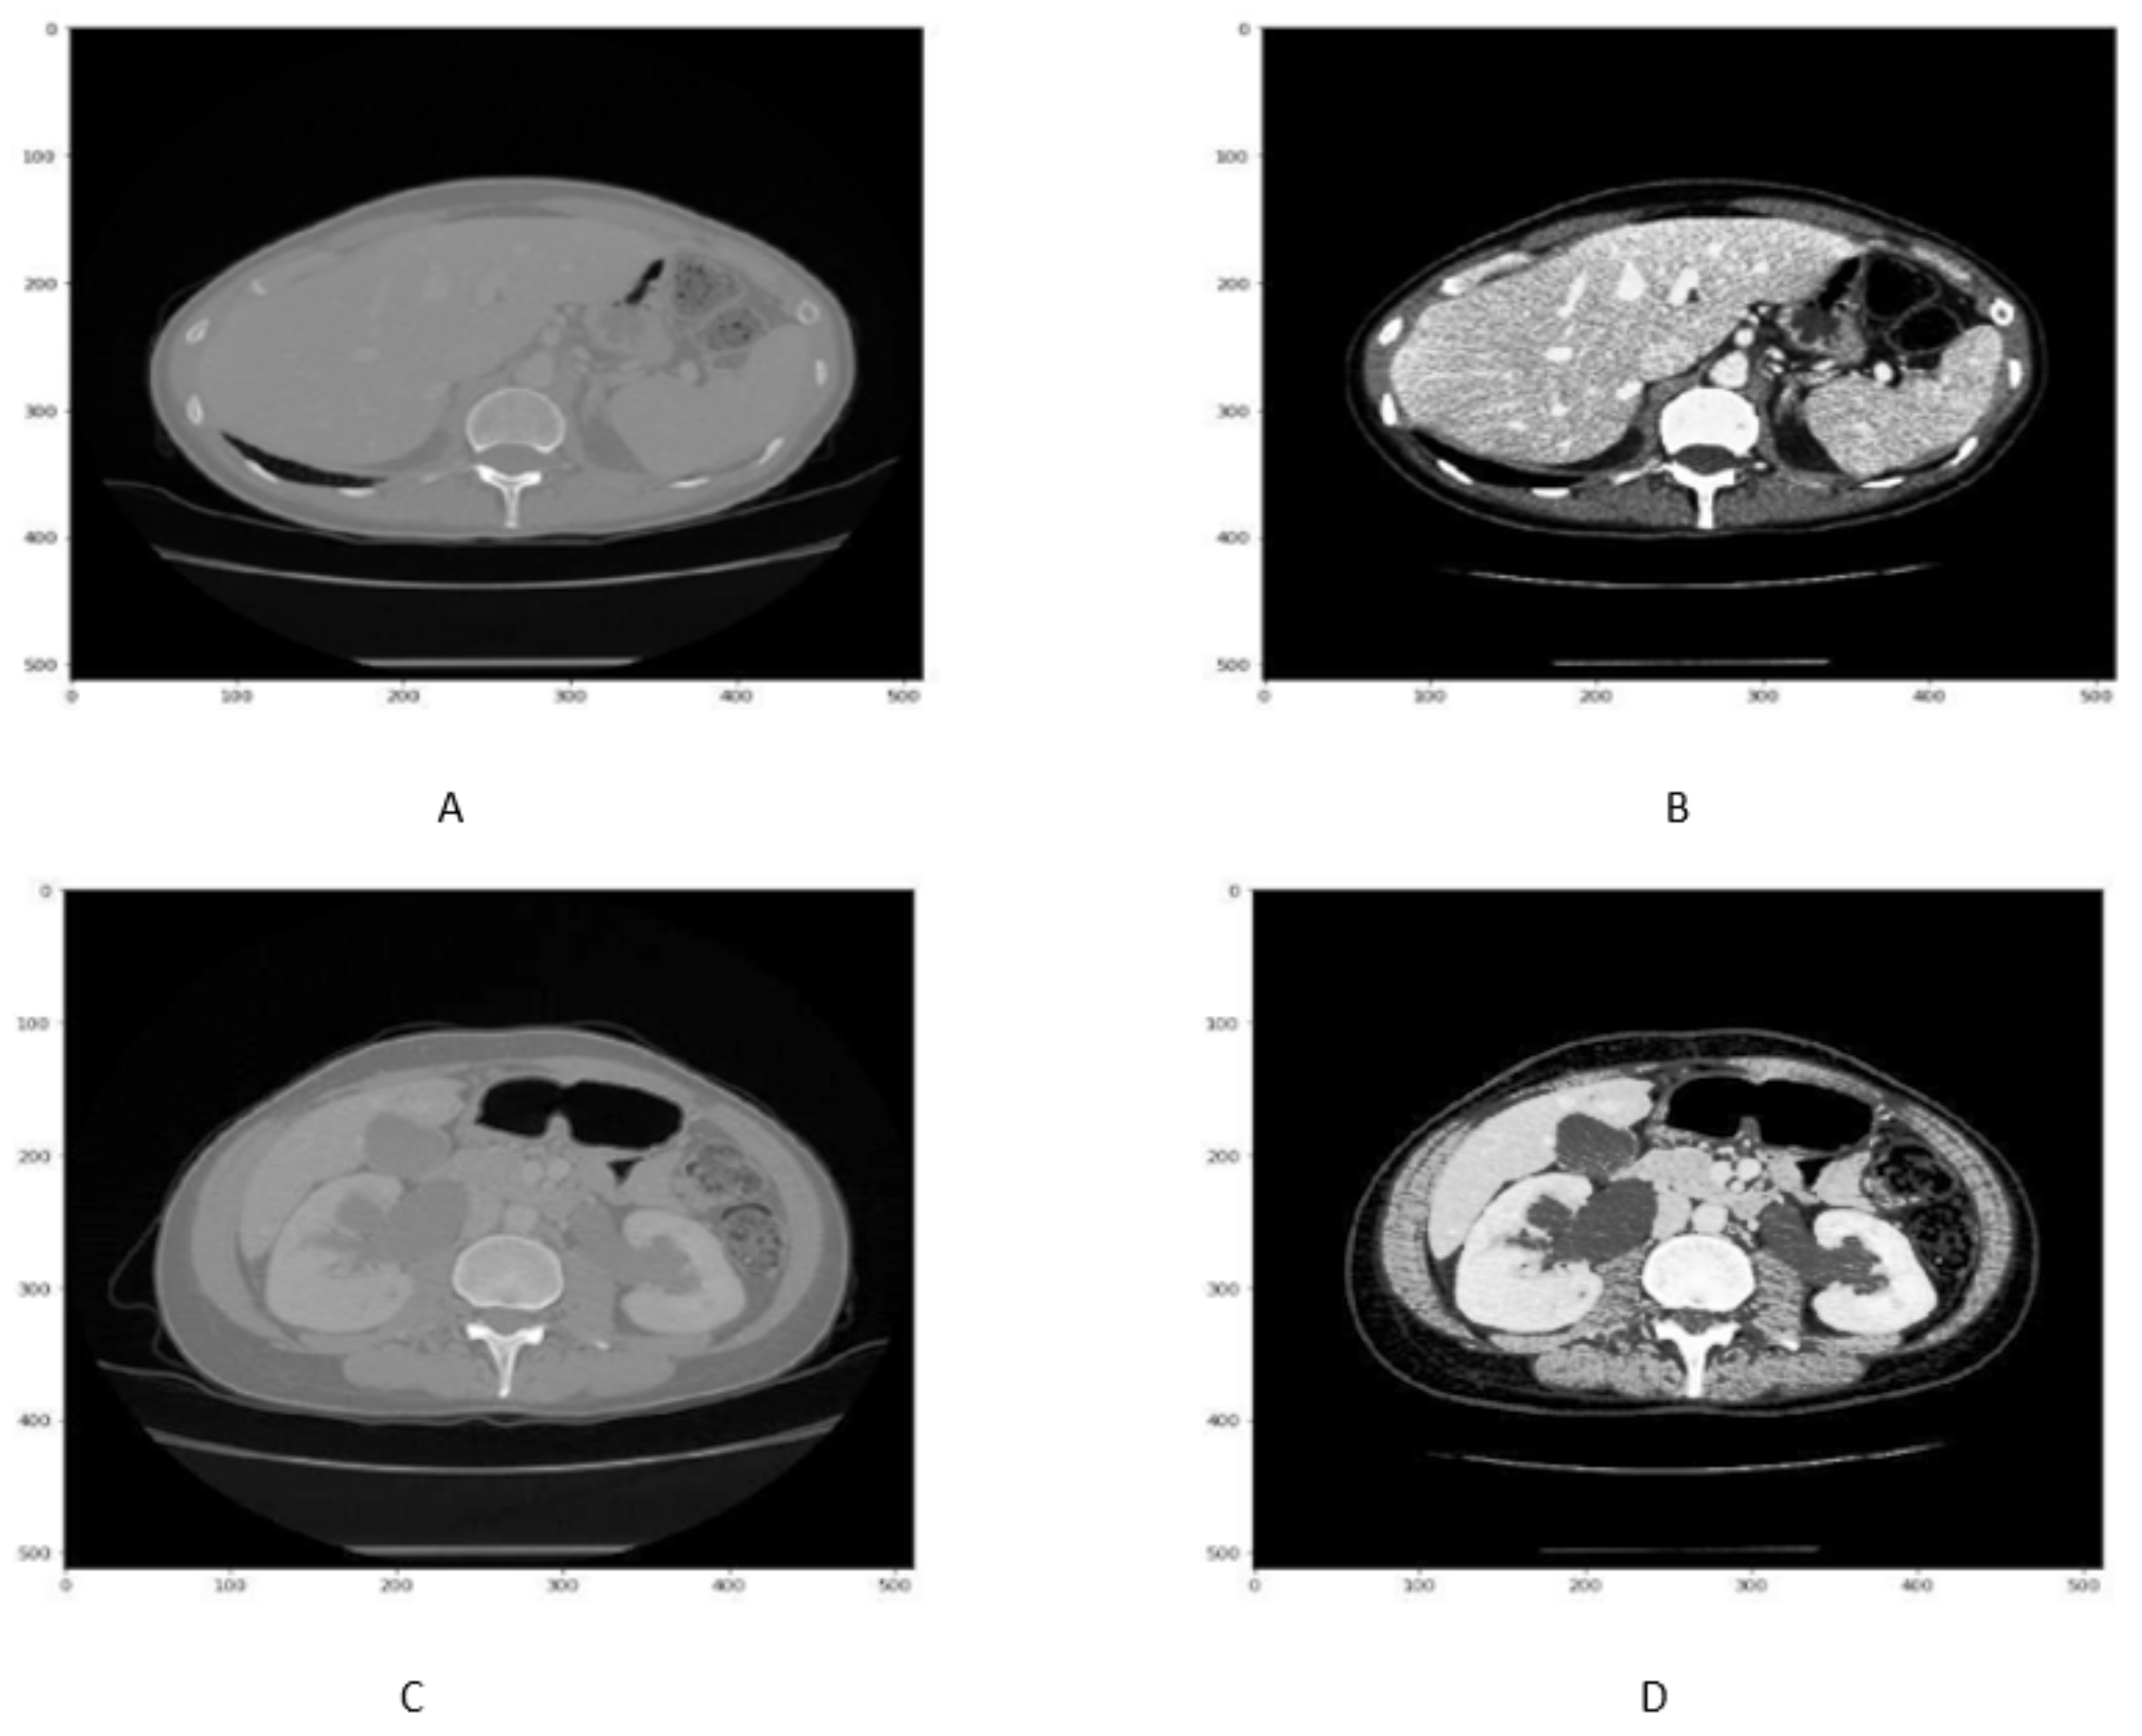

Reflection is a data augmentation technique in which the image can be flipped across the x or y-axis to generate more samples for network training. In order to avoid the computational expense, the liver images along with its tumor masks are reflected as shown in Figure 4A–F.

Figure 4.

Figure shows that the Liver scan tumor mask before 90 in (A,C,E) While liver scan and tumor mask in (B,D,F) after reflection.

3.3.2. Rotation

The rotation method of data augmentation involves rotating the image to a certain degree that can be considered a new image.Here, a 90 rotation of liver images along with its masks are performed as shown in Figure 5A–F.

Figure 5.

Figure shows that the liver slice and its masks before 90 in (A,C,E) rotation, While liver scan and its masks mask in (B,D,F) after rotation.